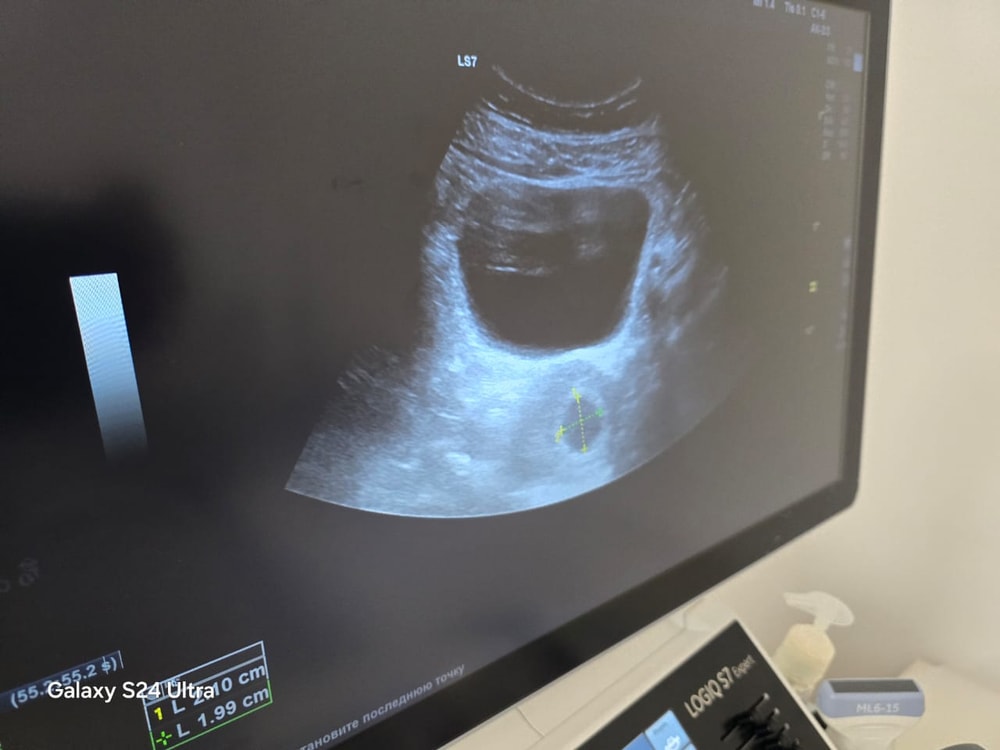

Узи на 7.3 недель

Обследования, узи, анализыВсем привет. Была на УЗИ трансобдоминально через животик (Вагинально у нас не делают нет специалиста) Увидели ПЯ ф 2.1см и больше ничего не сказал врач но он не гинеколог сказал все нормально. Почему не видно Эмбриона? Читаю у многих на этом сроке даже сб есть уже🥹

Сфотала просто экран даже не выдали фотку распечатанную. Посоветуйте пожалуйста🙏 Последний дц 12.06 первую 2 полоску увидела 26.06. Может аппарат плохой? Специалист точно плохой смотрел то только где то секунд 10 сказал беременность есть и все дал бумажку.